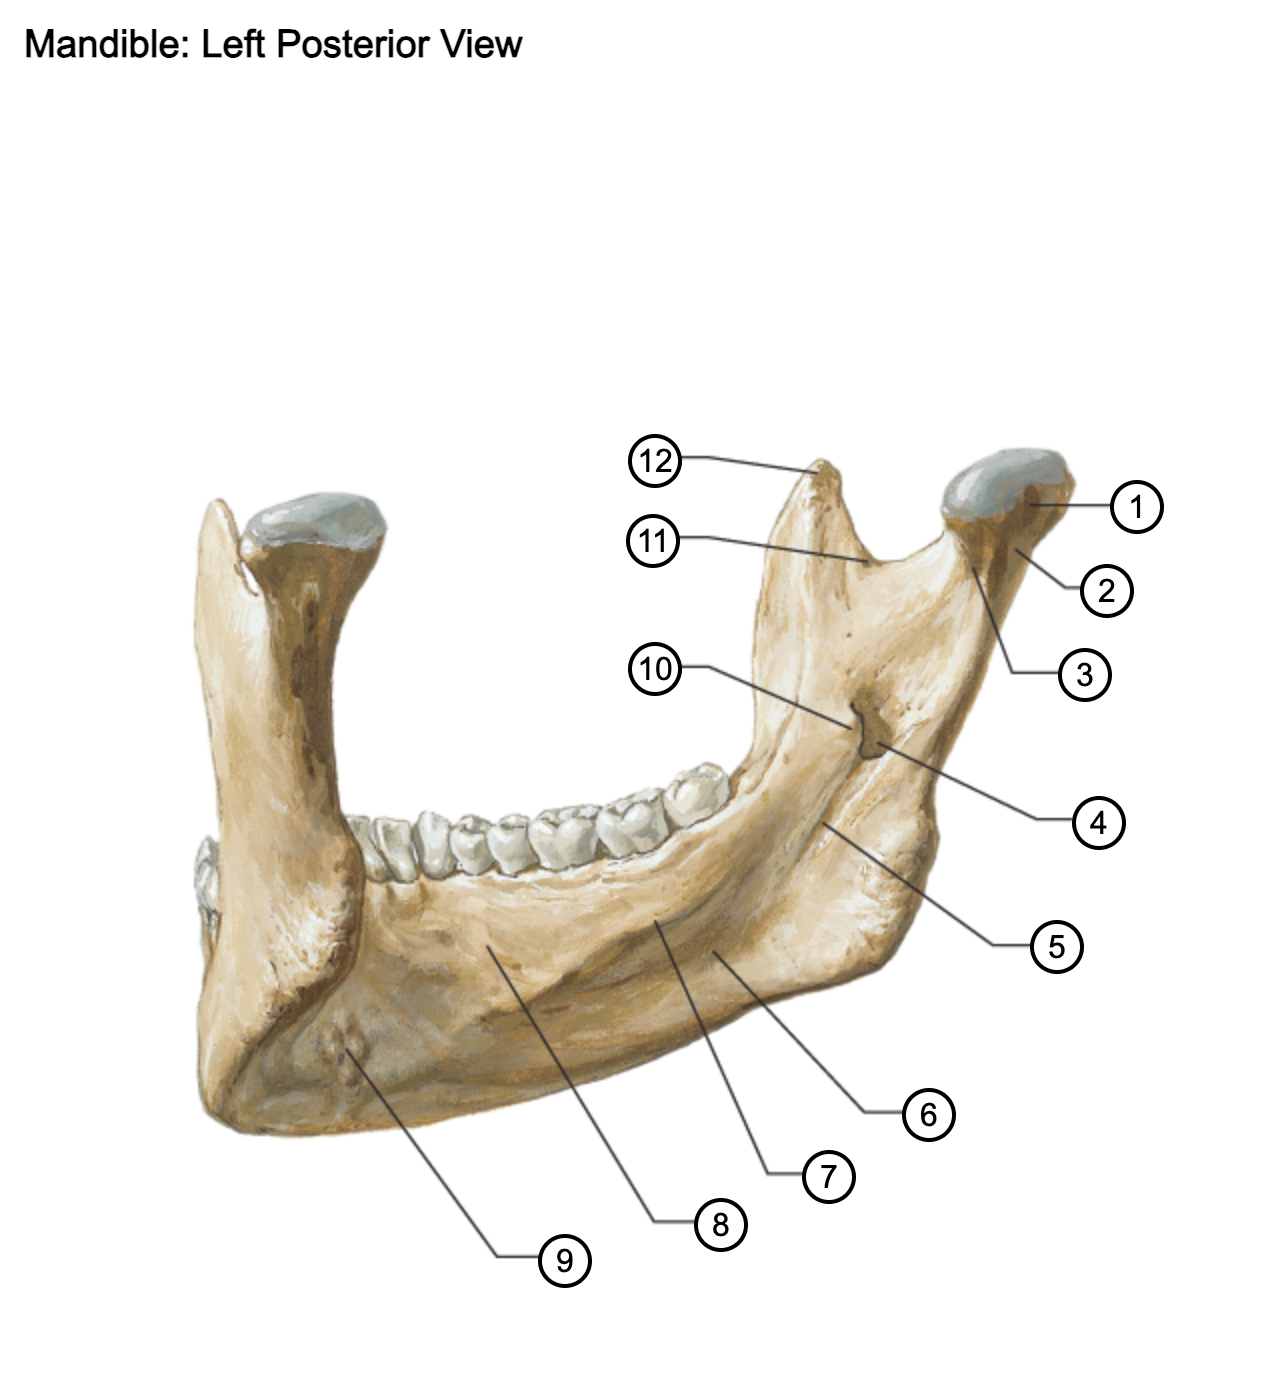

1

condylar process

2

neck of mandible

3

pterygoid fovea

4

mandibular foramen (inferior alveolar foramen)

5

mylohyoid groove

6

submandibular fossa

7

mylohyoid line

8

sublingual fossa

9

superior and inferior mental spines

10

lingula